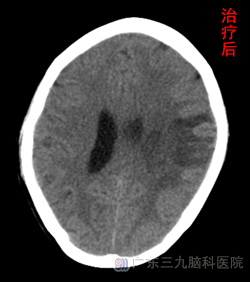

入院当日行头颅CTA示左侧额顶叶出血(亚急性期),颅内未见明确动脉瘤及畸形血管征象。外院MRV及我院CTA均不能确定是静脉还是动脉出血。于12月11日行DSA检查显示:左侧横窦、乙状窦血栓形成,动脉期血管未见明显异常。检查后确定为静脉血栓形成引起脑出血,给予足量、长疗程低分子肝素钙抗凝,经治疗1周后患者意识转清,D-二聚体(D-dimer)2.7mg/L。治疗1个月患者言语恢复流利,右侧肢体能抬离床面,复查头颅CT示现左侧额顶叶内出血及水肿较前有吸收,占位效应较前减轻(见对比图)。www.999brain.com

2013年1月7日,肖女士得以康复出院,出院时语言流利,右侧肢体活动灵活。(见对比图)